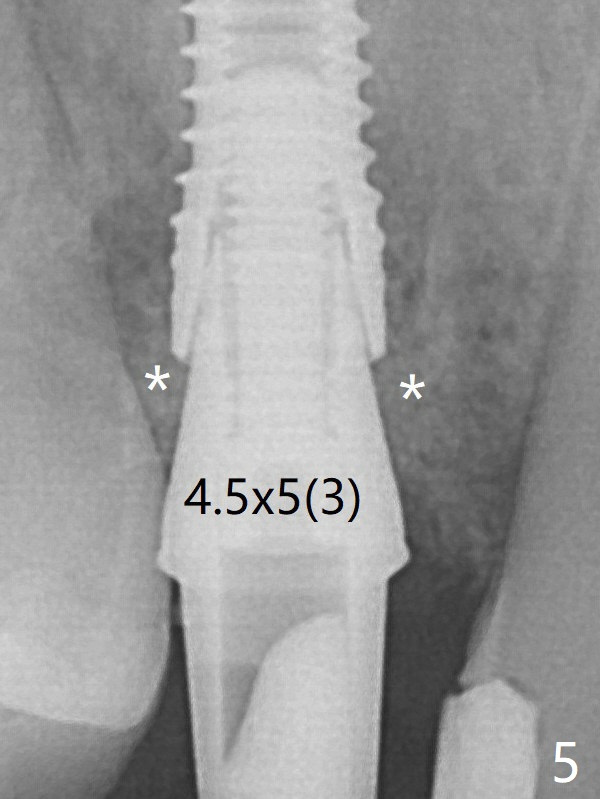

A final implant (3.8x15 mm) is placed with > 50 Ncm (Fig.4).  Before and after placement of a 4.5x5(3) mm abutment, Vera graft is placed in the remaining socket space (mainly buccal, Fig.5 *).  As routine, an immediate provisional is fabricated with occlusal clearance.  The bone graft appears to remain in place 4.5 months postop (Fig.7).  The bone density around the coronal portion of the implant increases 9 months postop (4 months post cementation, Fig.8).